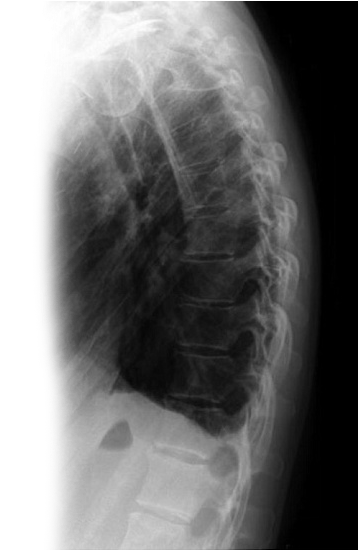

Рентгенография органов грудной клетки – распространенный метод скринингового исследования органов грудной клетки.

1. Рентгенография органов грудной клетки в 2-х проекциях - скрининговое исследование органов грудной клетки, выполняемое в двух проекциях.

2. Рентгенография легких в прямой проекции – скрининговое исследование органов грудной клетки, выполняемое в двух проекциях.

3. Прицельная рентгенография органов грудной клетки – исследование позволяет оценить наличие воспалительных, травматических, опухолевых, профессиональных (силикатоз, асбестоз) изменений легких.